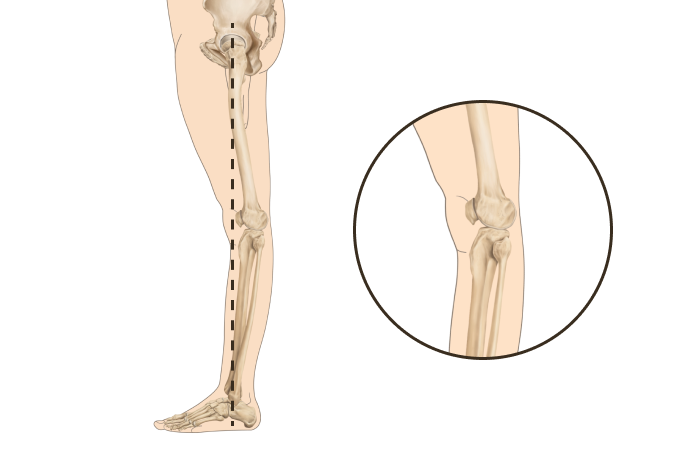

측면부에서 휜다리의 정렬에 따라

정상

신전형 (Back knee)

무릎 정상패턴과 신전패턴 2가지

휜다리는 단순히 무릎 사이 간격이 벌어진 것이 아닙니다.

무릎 위의 대퇴골과 아래의 정강이뼈가 회전하면서 무릎까지 뒤로 빠지기 때문에 다리사이 간격이 넓어지는 겁니다.

당당 휜다리

발(아치)-발목-무릎관절-고관절-골반의 서로 다른 회전을 바로 잡는 기술입니다.